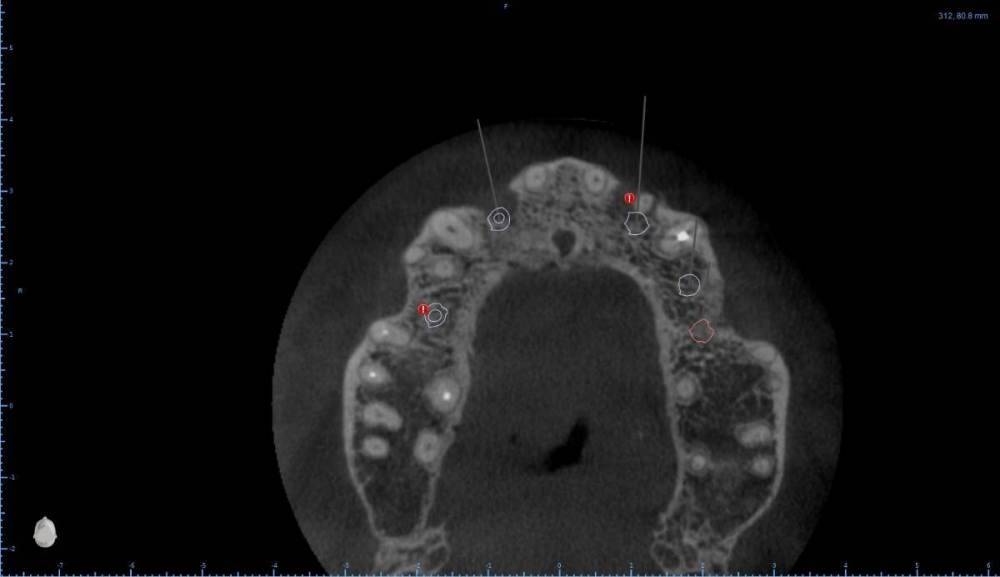

Женька Опубликовано 6 августа, 2022 Поделиться Опубликовано 6 августа, 2022 В общем планируется большая (по крайней мере для меня) работа. Вот такой товарищ у нас. Делали бы НКР в области 2.5з? или поставили бы чисто по кости, а оголённый участок закрыли присыпкой и мембраной? Также вопросы по двойкам имеются. Бугор есть, сразу оговорюсь, правда только с одной стороны. Также не понятно пока "как его правильно готовить" этот бугор, чтобы закрыть такие дефекты вестибулярной пластинки. Скрины постарался нарезать по максимуму. Там ещё будет ортодонтия конечно же. Интрузии, движения всякие и тд) Да, знаю, что планировать без цифрового гипса неправильно, но что имею. Ссылка на комментарий

Irouil Опубликовано 6 августа, 2022 Поделиться Опубликовано 6 августа, 2022 Если будет ортодонтия, то не проще ли вытянуть двойки чтобы вырастить ткани? ИДР тут нужен основательный очень, винты придётся крутить тоже очень длинные В области премоляра не вижу смысла что-то графтить, если хочется чего-то натолкать - можно стружки со сверла упаковать в дефект, но имхо не обязательно. А если сместить винт небно и чуть аннулировать, преп только пилотным и дальше конденсировать... ну Вы поняли 1 Ссылка на комментарий

Женька Опубликовано 6 августа, 2022 Автор Поделиться Опубликовано 6 августа, 2022 (изменено) @Irouil ортопед вряд ли согласится на такое. Может тогда проще пойти отсроченно? Удалить, кюретаж, губку в лунки и мэриленд (каппа с зубами) на 3 месяца. А потом уже выдумывать пластики по факту новой КТ? Винты 14мм максимум что есть По премоляру вот тоже думаю, что игра не стоит свеч. А двойки... признаться я уже ортопеду сказал, что отсрочено пойдём... хотя конечно пока всё ещё раздумываю Изменено 6 августа, 2022 пользователем Женька Ссылка на комментарий